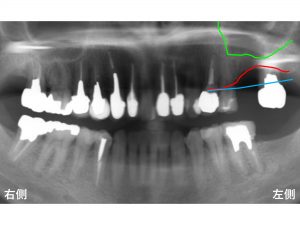

わかりやすいように骨吸収の状態を線でかいて見ます。

以下の青線が骨吸収する前の元々の骨の位置です。

現在の骨吸収した状態が以下の赤線です。

そして緑線が上顎洞の一番下の部分です。

この3つの線を組み合わせたのが以下です。

現在のように骨吸収している場合には、

インプラント治療が困難となります。

これではインプラントが長持ちするはずがありません。

そこで上顎洞の空洞の中に骨を増大させる治療が行われます。